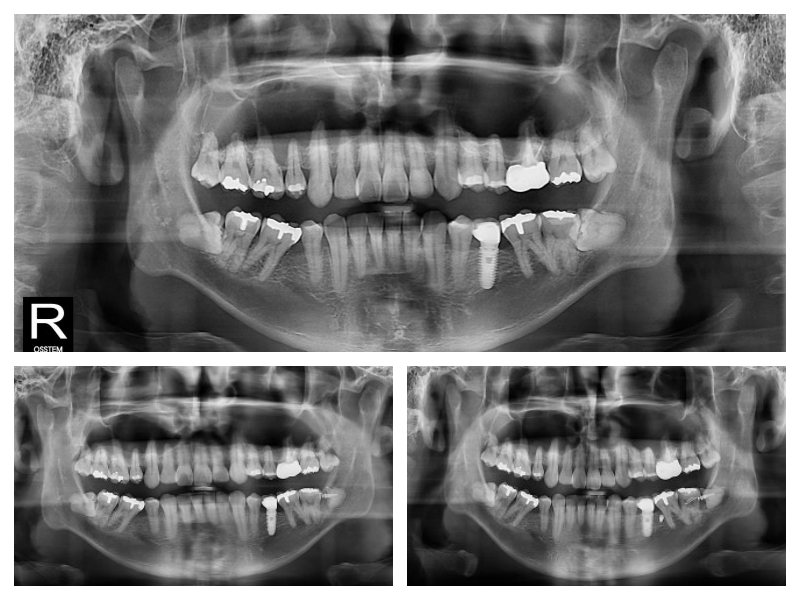

사랑니의 쓸모를 찾아서~

사랑니가 옆으로 누워있고 신경이라 가까워서 큰 병원 가서 뽑으래요~

사랑니뽑을 때 신경손상 나도 무섭다